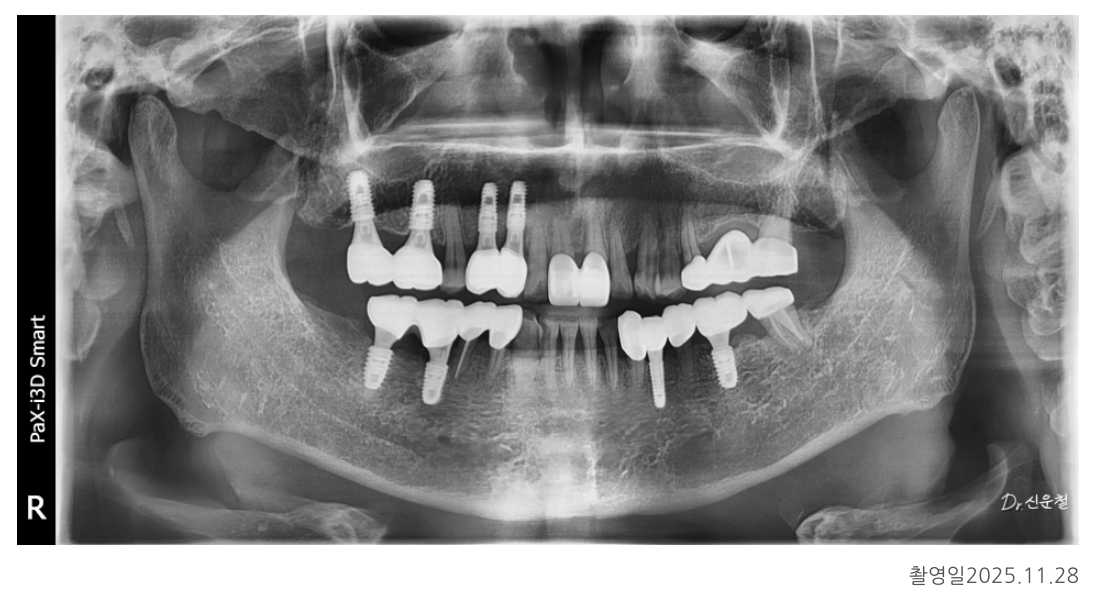

최종 결과: 전체 균형을 다시 회복

임플란트와 보철 치료가 모두 자리 잡은 뒤

다시 촬영한 사진에서는

✓ 양쪽으로 균형 있게 씹을 수 있는 교합

✓ 앞니·어금니의 힘 분산 안정

✓ 정출·기울기 문제 해결

이 확인되었습니다.

환자분은 총 5개 부위에 임플란트를 먼저 식립했습니다.